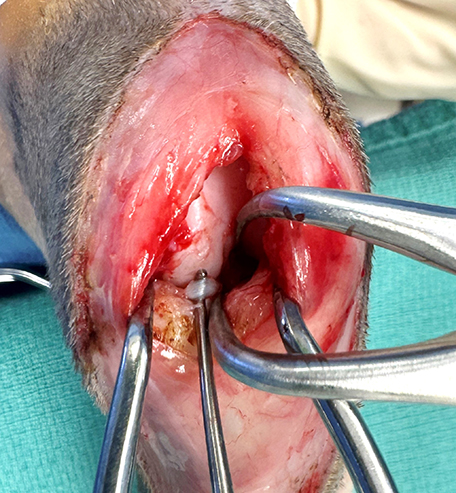

Meniscal damage occurs in up to 67% of cats with CrCL rupture (Ruthrauff et al, 2011); therefore, surgery for meniscal assessment and concurrent stifle stabilisation has been recommended (Figure 3). While, as was mentioned previously, the presence of meniscal calcification alone is not necessarily an indication for surgical intervention, as cats with larger mineralisations show more signs of joint degeneration, including specifically, degenerative changes in the CrCL, such cats may be more likely to benefit from surgical exploration.

A biomechanical study (De Sousa et al, 2015) showed that suture anchors placed in the caudal aspect of the lateral femoral condyle are comparable to using the femoro-fabellar ligament as an anchor point, and this has become my preference due to concerns about how firm an anchor point the lateral fabella is in this species (Figure 4).